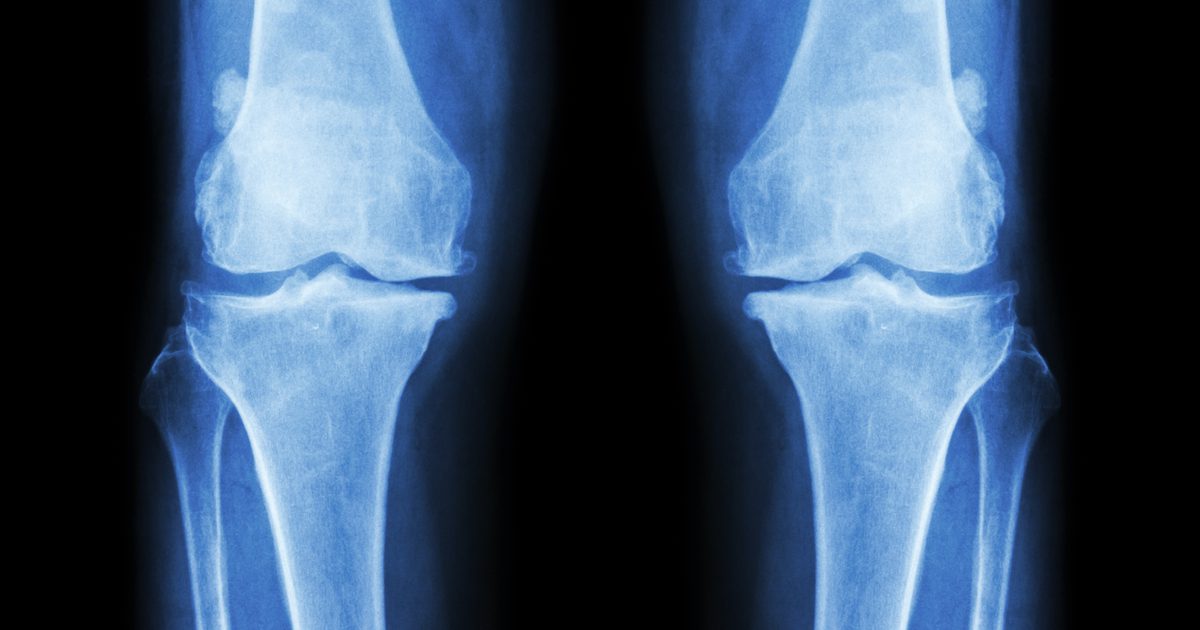

Bones

While the bones in your body are incredibly durable, accidents do happen causing them to break. The types of breaks a bone can suffer vary from case to case, but often times they are quite difficult for doctors to repair. The road to recovery can be a long one as different techniques are applied throughout the patient’s healing time, thus delaying the entire process.

Doctors are now given the capability of producing exact models of these fractures, allowing for time to study them and discover the best solutions as to how the bone can be reconstructed. They can also use the models to try and find new and more efficient methods to repair these complex breaks, rather than remain dependent on more traditional techniques.